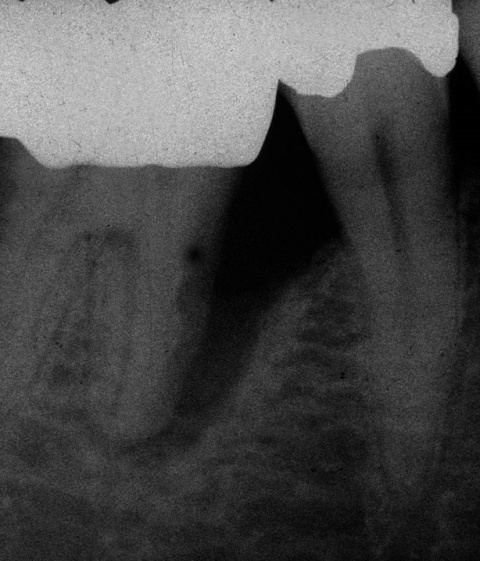

Durch eine Vielzahl von Studien konnte belegt werden, dass die Versorgung mit implantatgetragenem Zahnersatz eine bewährte Behandlungsoption darstellt. Gleichwohl zeigen viele Studien jedoch, dass – wie bei allen Therapiemaßnahmen auch – Komplikationen auftreten können. Diese haben im Allgemeinen biologische oder technische Ursachen. Als häufigste biologische Komplikation findet man die Mucositis (Abb. 1), die Entzündung der periimplantären Gewebe ohne Beteiligung des Alveolarknochens. Nach aktuellen Studien weisen ca. 30 % aller Implantate nach fünf Jahren eine Mucositis auf. Kommt es darüber hinaus zu einer Beteiligung des Alveolarknochens, liegt eine Periimplantitis vor (Abb. 2). Sie tritt nach fünf Jahren bei etwa 10 % der inkorporierten Implantate auf und ist durch den Verlust des periimplantären Alveolarknochens gekennzeichnet. Die Periimplantitis kann, je nach Schweregrad, zum kompletten Implantatverlust führen. Bei einem strategisch wichtigen Implantat kann daraus der Verlust der gesamten prothetischen Versorgung resultieren und eine operativ sowie finanziell aufwendige Neuversorgung erforderlich werden (Abb. 3).

Neben den biologischen Ursachen können auch technische Schwierigkeiten auftreten. Dabei ist die komplette Fraktur eines Implantats (Abb. 4) zweifellos die schwerwiegendste, sie tritt aber nur sehr selten auf. Häufiger sind Schraubenlockerungen und Schraubenfrakturen, wobei letztere in Abhängigkeit von der Lokalisation der Fraktur ebenfalls den Verlust eines Implantats zur Folge haben kann.